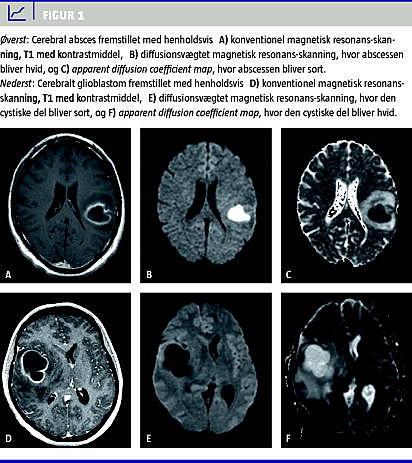

Ved DWI bruges de cystiske/nekrotiske områders signal til at skelne mellem absces og cystisk tumor (Figur 1 B og 1E). Indholdet i en absces vil have nedsat diffusion og vil på DWI ses som et område med højt signal = lyst (sammenlignet med CSF, som har høj diffusion og dermed er mørkt, Figur 1B). Indholdet i en cystisk/nekrotisk tumor har derimod ofte høj diffusion ligesom vand, hvilket giver et lavt signal = mørkt (igen sammenlignet med cerebrospinalvæsken i ventriklerne, Figur 1E).

Apparent diffusion coefficient (ADC) beregner de fleste MR-skannere selv ud fra DWI-skanningen. Her er signalet lige omvendt, dvs. at nedsat diffusion giver et mørkt område, og høj diffusion giver et lyst område. Abscessen er derfor mørk, mens cerebrospinalvæsken er lys (Figur 1C). Den cystiske/nekrotiske tumor er lys som cerebrospinalvæsken (Figur 1F). For både DWI og ADC gælder, at den cystiske tumor har samme signal som cerebrospinalvæsken, mens abscessen har det modsatte signal af cerebrospinalvæsken [1].